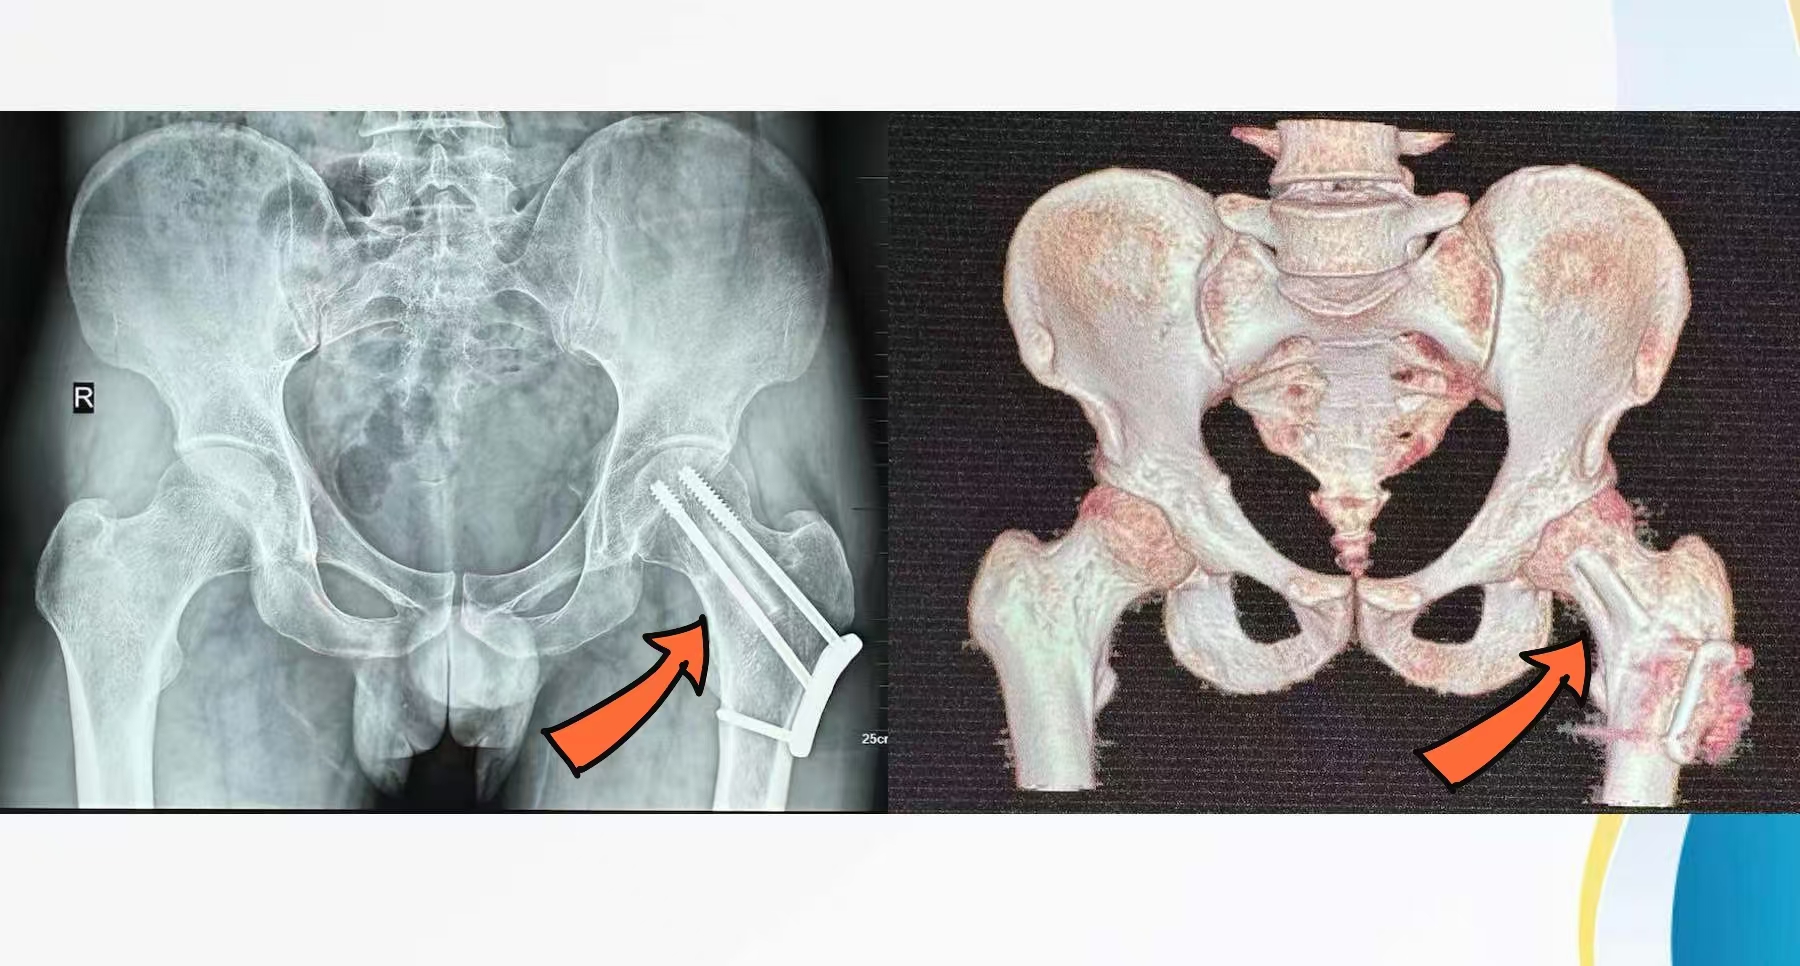

术后X光片/术后三维CT影像

针对具体病情,骨科主任姬传磊向患者介绍了一种新兴的治疗方式——带血管腓骨移植术。该手术非常复杂,需要分离腓骨上的血管,连同腓骨一起移植到受损部位,再与原有的血管和骨骼进行精细连接。征得张先生和家属同意后,姬传磊团队着手实施手术,在显微镜下吻合血管3根。经姬传磊团队的密切协作,手术顺利完成,患者安返病房。